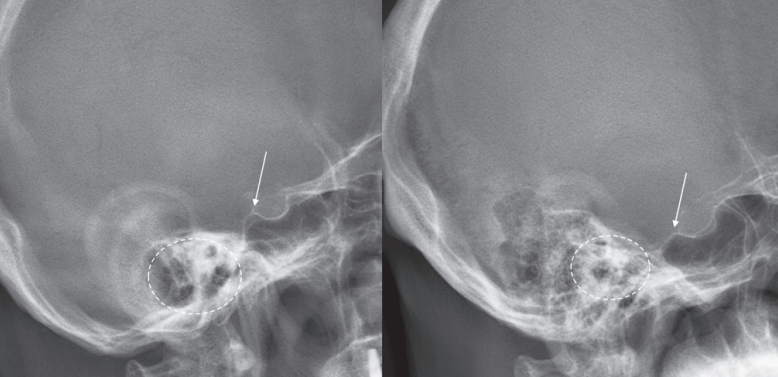

Original ArticleJun 30, 2025

Validating the Reliability of External Auditory Meatus as a Reference Point for Cranial Center in Spinal Deformity Patients: A Preliminary Report

Dongkyu Kim, Bong Ju Moon J Adv Spine Surg 2025;15(1):29-32. -